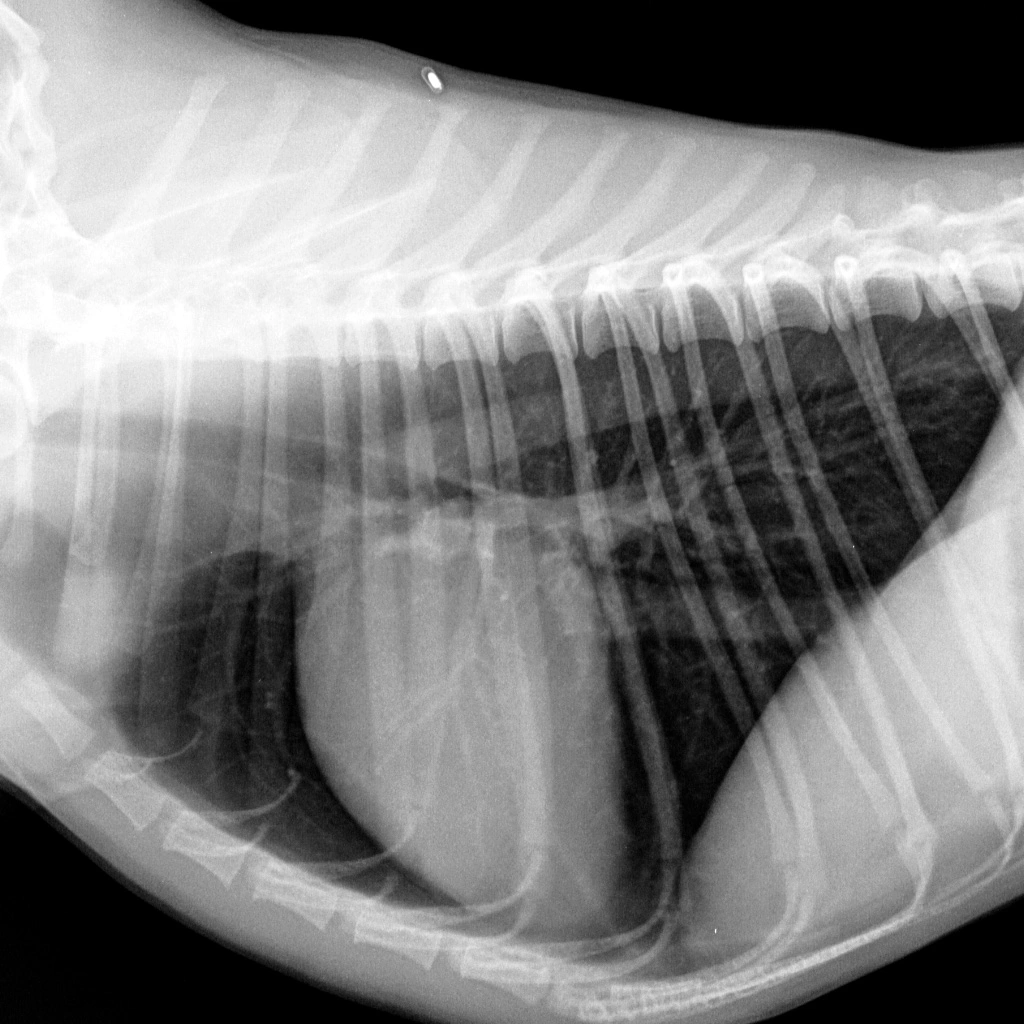

Отделение рентгенодиагностики оборудовано современной системой получения рентгеновских снимков и позволяет получать изображения грудной клетки в высоком разрешении (сердце, сосуды, легкие, трахея и др.). Это позволяет заметить даже незначительные изменения размеров сердца, новообразования маленьких размеров, верно оценить структуру тканей.